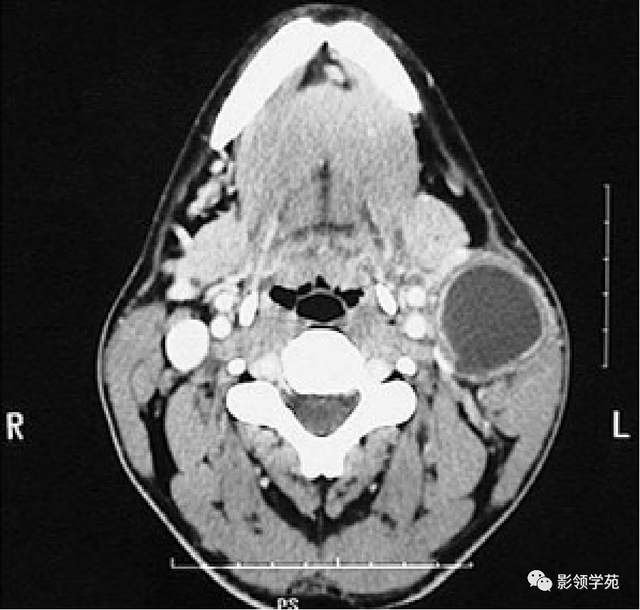

病例1:男性, 41岁,因“发现右耳垂下肿物1月余”:

病理:混淆瘤

病例2:女,30岁,发现右耳垂下肿物9月